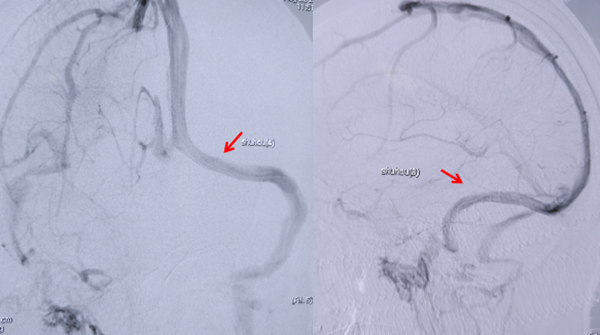

图2 支架植入后狭窄解除(箭头处),血流通畅,两端压力差基本消失